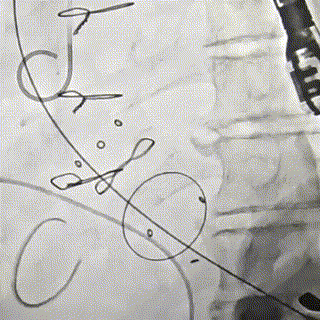

DSA下钢针穿刺心尖,建立心尖入路

输送系统沿加硬导丝进入

瓣膜初次释放,位置稍浅

目标深度:瓣环平mark点

部分回收后,调整瓣膜深度重新释放,瓣膜位置良好

无张力脱钩,瓣膜位置稳定

闭合输送系统后撤除体位,

收紧心尖荷包